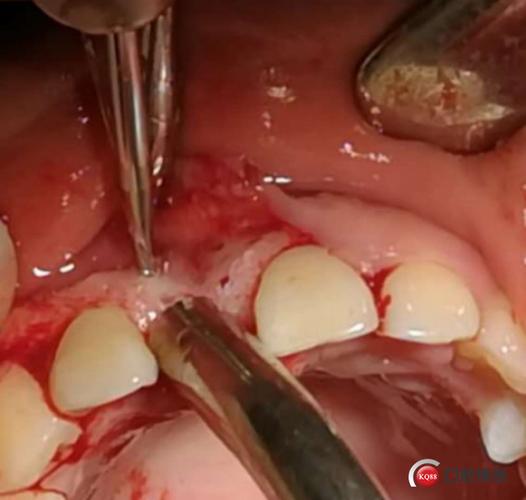

唇侧用球钻开孔,去骨皮质化,为骨替代材料提供血供来源.